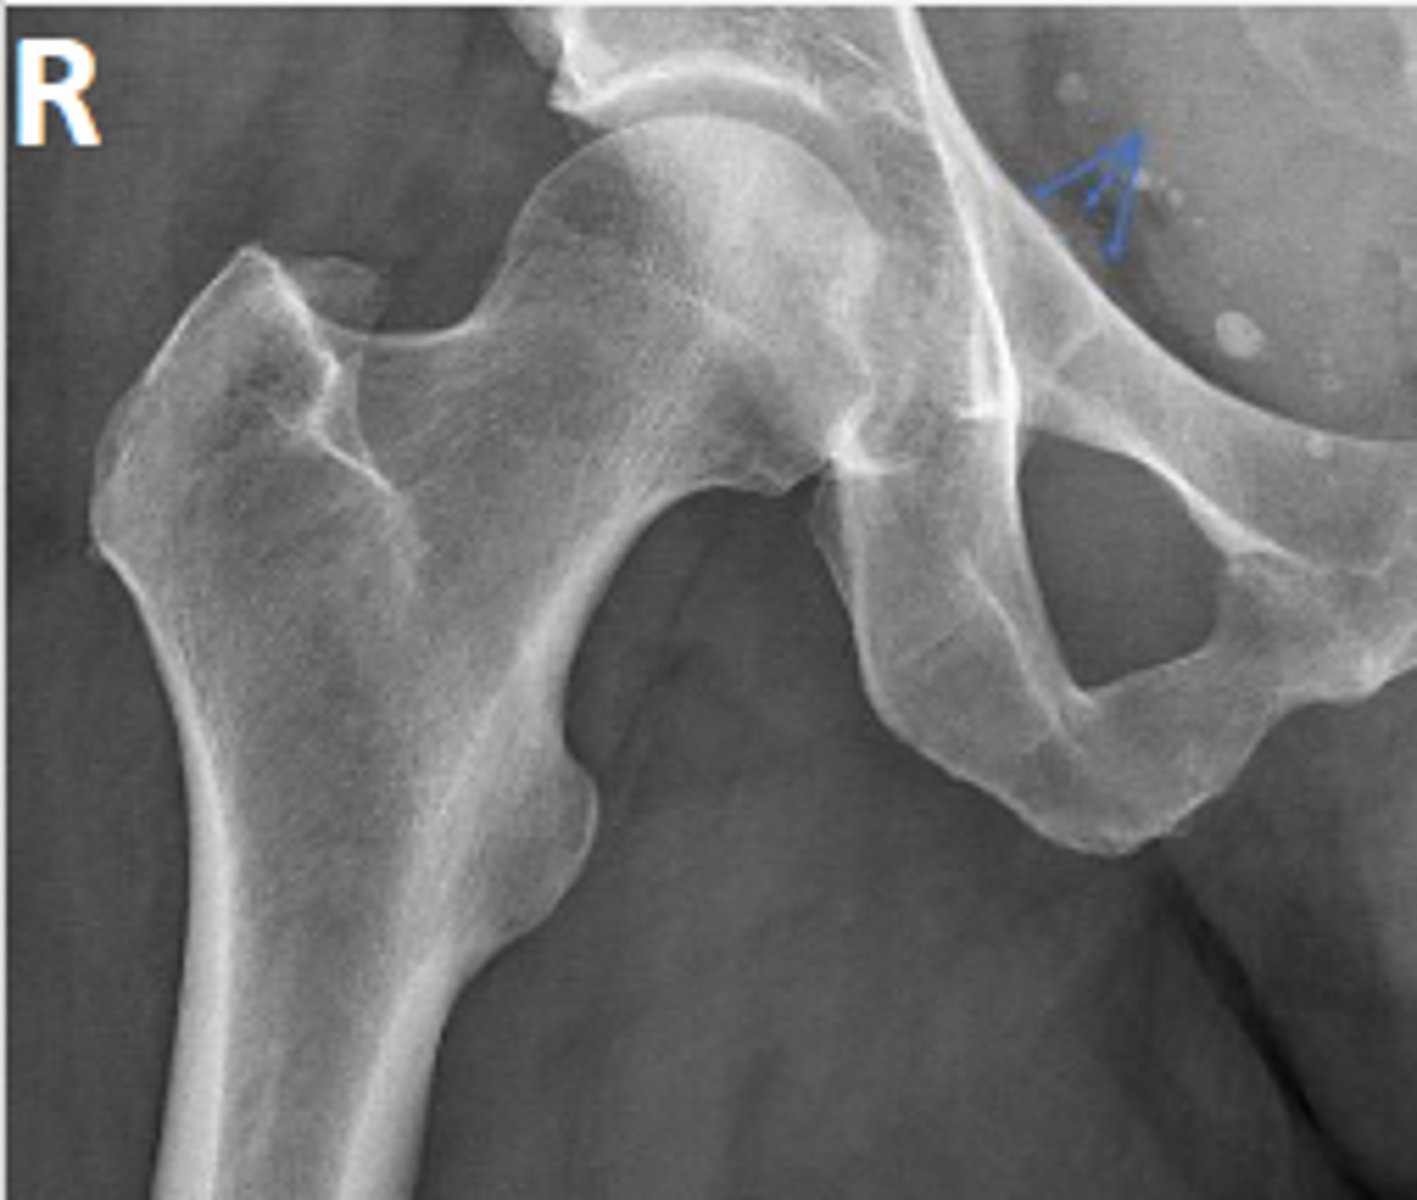

Right AP hip

What is the name of the radiographic view?

Right posterior inferior iliac spine

What are the arrows pointing to?